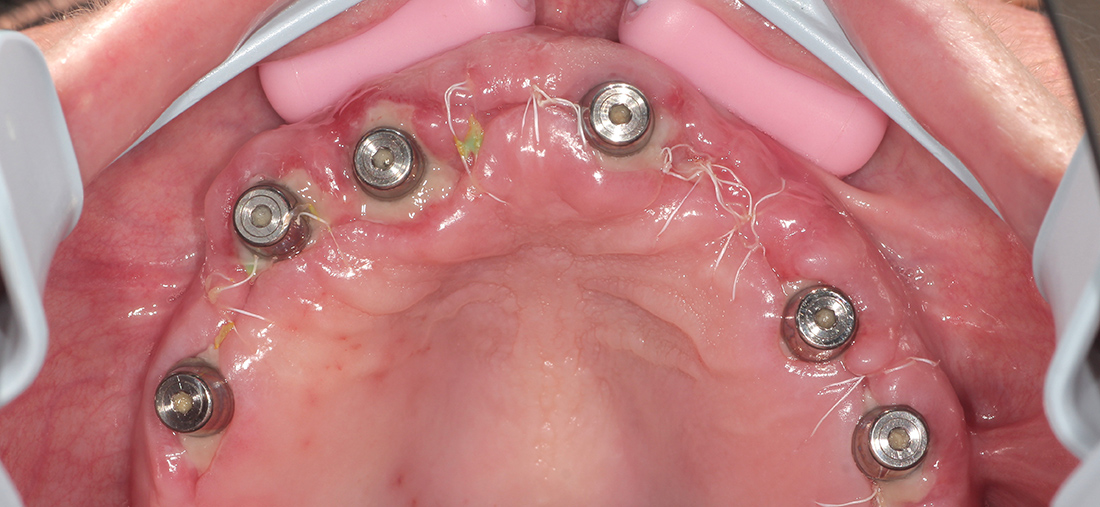

В данной ситуации мы зафиксировали шаблон, установили 6 имплантов системы «ICX Templant» (Германия), провели наращивание костной ткани, установили окончательные головки «мультиюнит» и сняли слепки для изготовления временной конструкции. Через несколько дней был готов металлопластмассовый протез с винтовой фиксацией на шести имплантах.